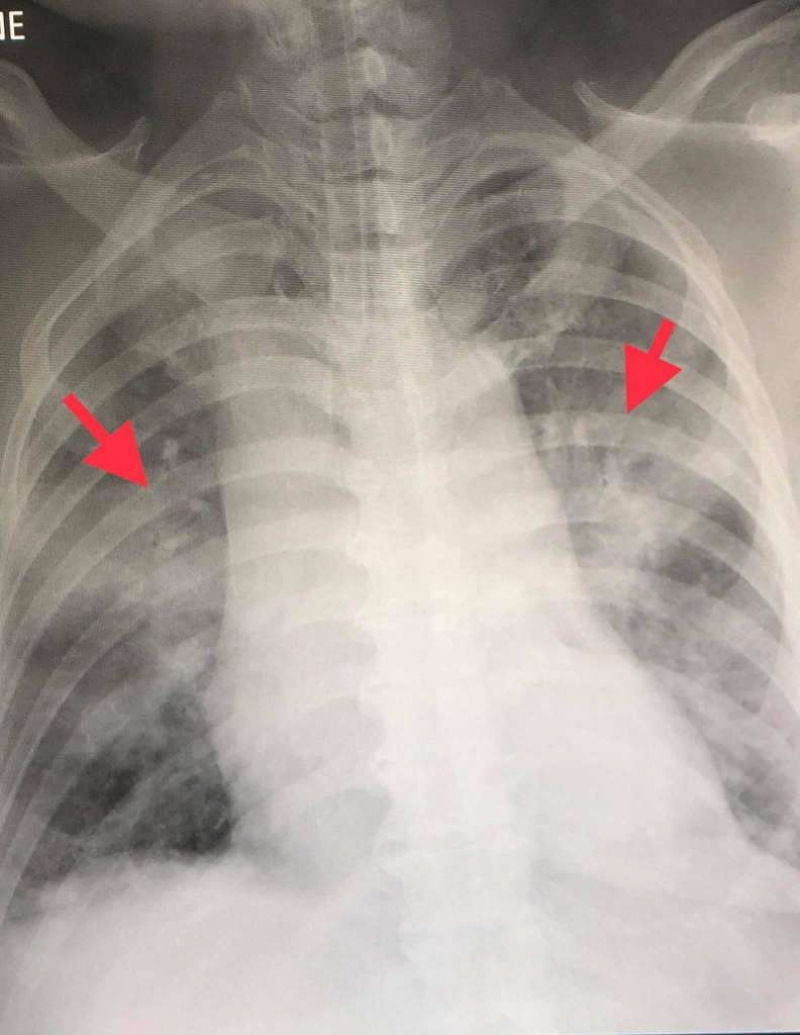

สาเหตุที่สำคัญน่าจะเป็นจากเชื้อไวรัสโควิด-19 ในประเทศอิตาลีเป็นเชื้อสายพันธุ์ที่ดุร้ายกว่าประเทศอื่นในเอเชีย สามารถเพิ่มจำนวนในปอดได้รวดเร็ว ทำให้แพร่กระจายเชื้อให้ผู้อื่นมากขึ้น และเชื้อนี้เล่นงานปอดอย่างหนัก ทำให้ปอดอักเสบอย่างรุนแรง ระบบหายใจล้มเหลว อัตราการเสียชีวิตจึงสูงมาก

ประเทศไทยกำลังมีเชื้อโควิดที่ดุร้ายจากประเทศอิตาลีแพร่ระบาด ยอดผู้ป่วยติดเชื้อรายใหม่ ดูรูป และผู้เสียชีวิตจากปอดอักเสบกำลังจะเพิ่มขึ้นอย่างรวดเร็ว สำหรับผู้ป่วยที่ติดเชื้อโควิดรายใหม่ที่เกี่ยวข้องกับสนามมวย แพทย์คงต้องให้ยาต้านไวรัสตัวใหม่จากประเทศญี่ปุ่น ชื่อยา Avigan คือฟาวิพิราเวียร์ Favipiravir และยาอื่นๆเช่น hydroxychloroquine เพราะผู้ป่วยรายใหม่กลุ่มนี้จะมีปอดอักเสบมากขึ้น ถ้าไม่ให้ มีโอกาสปอดล้มเหลวสูง